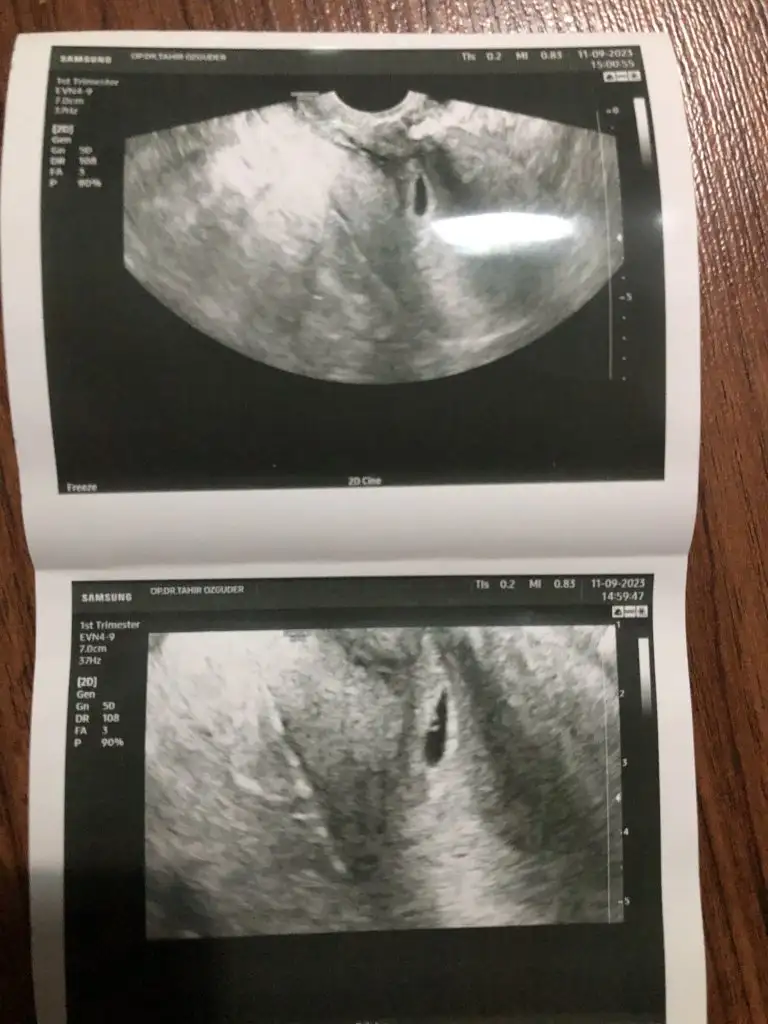

cok gecmıs olsun cnım bebısını gorup kalp atısını duydun dımıPerşembe yada cuma gel dedi canım. İlki kanama alanı digeri kese

Evet kuzum gördün mü sende bebegi doktor söylemedi ama ben o soldaki nokta gibi olan şeyi bebege benzettim hemde plesentası solda bebek sagda erkek oluyorKuzum kesenın ıcınde bebek olusmaya baslamıs,gordunmu sende gecen gıttıgıne gore fark var.lütfen dınlen bak cocuklarda okula baslamıstır sımdı gerekırse annenden fln yardım ıste bir müddet kalkma canım yat,kavusacaksın bebegıne ben ınanıyorum Allahın ıznıyle

Yok kuzum daha 5+0 zaten bugün karından kese görmeye gidecektim dün akşam kanamam olunca sabah gittim progesteron içiyorum sabah akşmcok gecmıs olsun cnım bebısını gorup kalp atısını duydun dımı

kanama alanı evet cok tehlıkelı ama kendını yormuyorsun hıcbır ıs yapmıyorsun sureklı yat ve progestan mı verdi pruloton mu

çok geçmiş olsun canım kacıncı haftada keseyi gördün resimlerde hiç sıkıntı görünmüyor umarım sağlıkla kucagına alırsınBen geldim kızlar neler yaşadım neler ufak bi özet geçeyim size. İlk devletteki doktoruma gittim ve keseyi yine göremedik alttan baktı belli belirsiz bi kese dedi geri gelişimi dedi çok korktum hemen özel bilindik bi doktorun muayenesine gittik ve çok şükür orda net gördük riskli bi gebelik ama hastasıyla uyumlu içinde yolk bile olduğunu söyledi korkulacak bir durum yok şuan için dedi ama eski sezeryan yerime yakın biraz aşağıya yerleşmiş 2 haftaya belli olucak herşey dedi 2 hafta sonra tekrar çağırdı lütfen dua edin de bi sorun olmasın kanama olabilir düşük olabilir hazırlıklı olun herşeye dedi ama şuanlık iyi maşallah

Vajinadan mı gördün kuzum sen bana karından baktıBen geldim kızlar neler yaşadım neler ufak bi özet geçeyim size. İlk devletteki doktoruma gittim ve keseyi yine göremedik alttan baktı belli belirsiz bi kese dedi geri gelişimi dedi çok korktum hemen özel bilindik bi doktorun muayenesine gittik ve çok şükür orda net gördük riskli bi gebelik ama hastasıyla uyumlu içinde yolk bile olduğunu söyledi korkulacak bir durum yok şuan için dedi ama eski sezeryan yerime yakın biraz aşağıya yerleşmiş 2 haftaya belli olucak herşey dedi 2 hafta sonra tekrar çağırdı lütfen dua edin de bi sorun olmasın kanama olabilir düşük olabilir hazırlıklı olun herşeye dedi ama şuanlık iyi maşallah

Ben 4+5 de vajinal gördüm canımçok geçmiş olsun canım kacıncı haftada keseyi gördün resimlerde hiç sıkıntı görünmüyor umarım sağlıkla kucagına alırsın